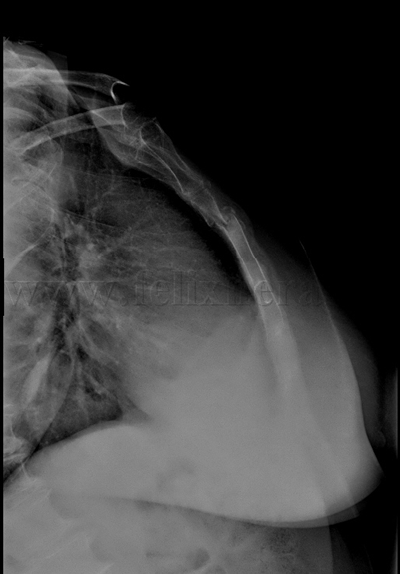

Fractura de esternón